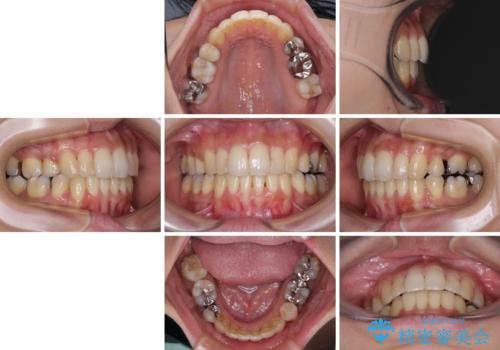

後戻りで突出した前歯をインビザラインで解消

- 抜歯矯正の後戻りで前歯が突出してきていることを気にして来院された患者様です。

口元の突出感を改善するにあたり、抜歯矯正は行うことができないため、奥歯の後方移動とIPR(歯と歯の間を削る)により達成することとしました。

再度後戻りしたときに対応しやすいよう、インビザラインにて矯正治療を行うこととしました。

舌の突出癖がなかなか改善できず、IPRによる前歯の隙間が閉じきらずに、予定よりも長い治療期間となりました。